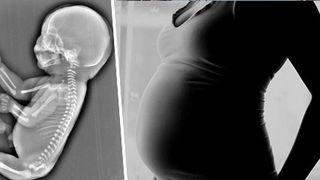

O femeie insarcinata in 6 luni a decis sa faca avort, dupa ce medicii i-au spus ca bebelusul pe care il poarta in pantec are o coada, in loc de picioare. Fetusul suferea de sirenomelie (Sindromul Sirenei).

In cazul acestui sindrom rar, picioarele bebelusilor sunt unite, luand forma unei cozi de sirena, de unde si denumirea de sirenomelie.

Sirenomelia, sau „sindromul sirenei” este o boala mortala. Copilul se naste cu picioarele unite intr-unul singur si intoarse. De obicei, micutii nu traiesc mai mult de cateva zile.